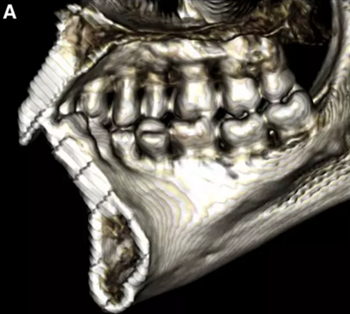

然而,CBCT成像也具有較大的限制:有限的分辨率,牙體組織的不準(zhǔn)確表現(xiàn),以及當(dāng)患者在咬合位或者完全牙尖交錯位CBCT掃描時,上頜骨和下頜骨牙齒之間發(fā)生的混合(圖1)。 這種混合使上頜骨與下頜骨牙齒的自動分離復(fù)雜化,并且由于咬合解剖結(jié)構(gòu)和細(xì)節(jié)的不準(zhǔn)確而使人工分離變得困難。

圖1. 在CBCT中咬合時上頜牙齒和下頜牙齒咬合面的混合和咬合細(xì)節(jié)的喪失。